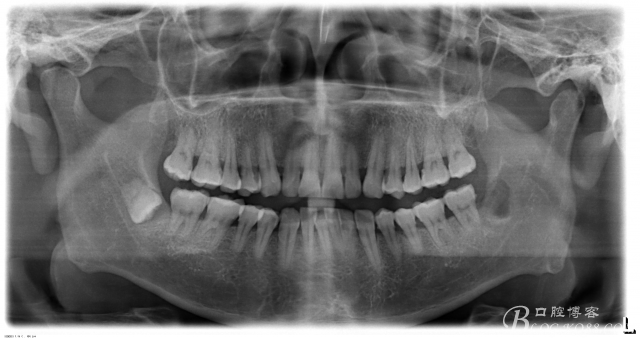

一、術(shù)前CBCT影像資料